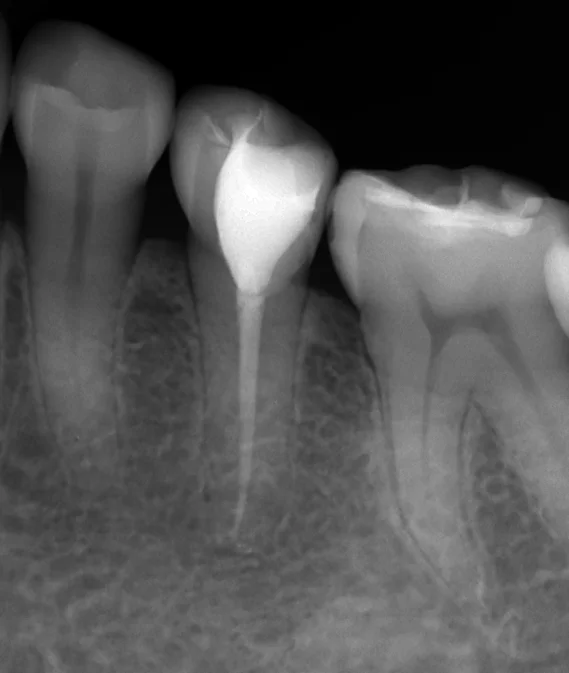

そして神経の治療を終わった直後のレントゲンがこちらです。

少し根の先から材料の一部が飛び出してしまいましたが、これは最終的な薬を根の管にくっ付ける為の接着剤で、割と早く吸収されるので特に害はありません。

1回目の治療と2回目の治療が3週間くらいしか開いていないので、根の先の膿が入っていた黒い影はまだ全く消えていません。

根の先のこの影は数年単位で膿がじわじわと骨を溶かして起こってくるものですので、神経の治療が終わった途端に骨が出来て、黒い部分が無くなる!という事はあり得ません。

大体治療から半年~1年経過して、ようやく治療が上手くいったかどうかが判断できます。